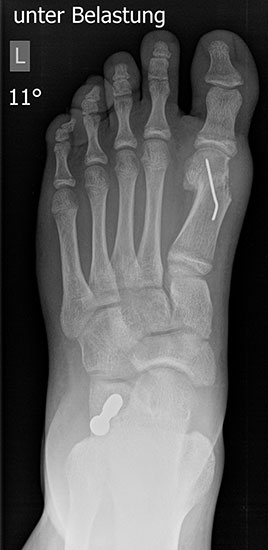

Standard ist die belastete Röntgenaufnahme des Fußes dorso-plantar und seitlich. Günstig ist eine Röhrenkippung von 10°-20°, um die Gelenke der Lisfranc-Linie einsehen zu können.

Ergänzend kann eine Schrägaufnahme hilfreich sein. Bei Metatarsalgien oder Pathologien der Sesambeine liefert die Sprinteraufnahme zusätzliche Informationen. Bei einer Pes planovalgus Fehlstellung wird ergänzend ein Saltzman view durchgeführt.

• Hallux valgus Winkel

• Hallux valgus interphalangeus Winkel

• Intermetatarsalwinkel I zu II

• Distaler Metatarsale Gelenkwinkel (PASA)

• Form des Mittelfußknochenkopfes

• Winkel Metatarsale I Basis zum Os cuneiforme mediale

• Metatarsalindex

• Elevation/ Plantarisierung I. Strahl

• Pes metatarsus adductus

• Wachstumsfugen

• Coalitiones

• Akzessorische Knochen